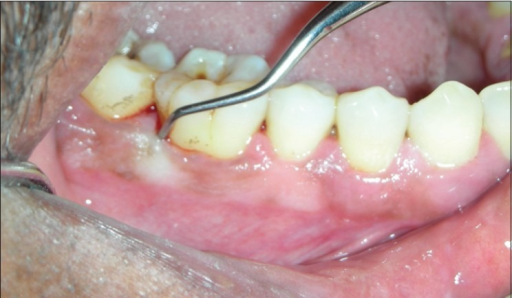

Descripción: Clinical examination revealed 7-mm probing depths, circumferentially around a mandibular implant, bleeding on probing, and the presence of exudate and gingival inflammatory edema